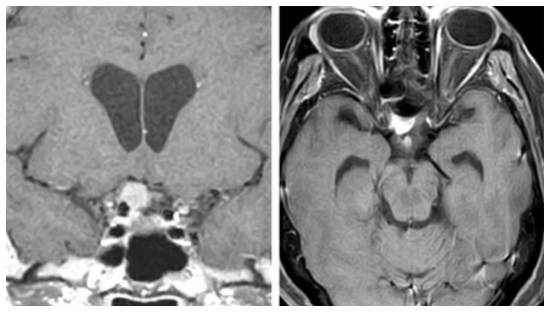

图2. 根据蝶骨嵴内侧型脑膜瘤是否侵犯内侧神经血管和包绕颈动脉穿支血管,可表现出不同的手术难度。上图所示为一例向内侧轻度延伸的脑膜瘤,侧裂大脑中动脉分支覆盖在肿瘤的上极。下图所示为一例真正意义上的蝶骨嵴/床突内侧型脑膜瘤,向内侧显著生长并包绕ICA。

图3. 一例第三组或右侧视神经孔脑膜瘤。肿块所处的关键位置导致相对快速的视力恶化,使得肿瘤在早期得以发现。

图4. 冠状位和轴位图片显示蝶骨嵴中部/内侧脑膜瘤与周围血管结构之间的典型关系。往往可发现更为明显的视器受压的证据。